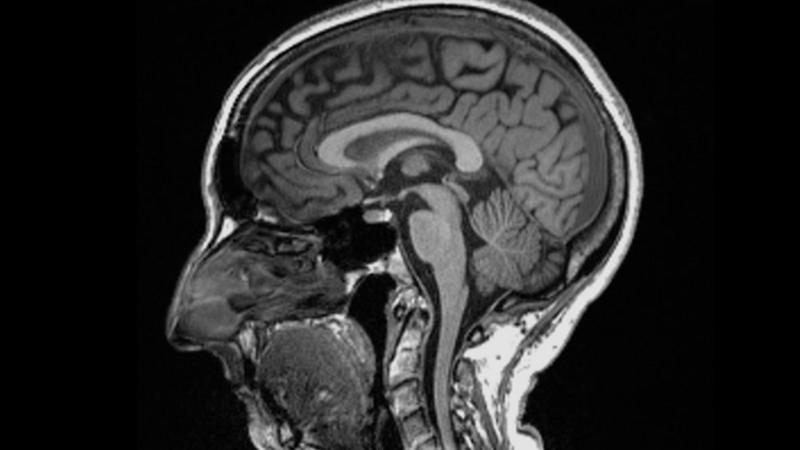

Oxford Üniversitesi’nde yapılan bir araştırma, COVID-19’un beynin küçülmesine, duygu ve hafızayı kontrol eden bölgelerdeki gri maddenin azalmasına ve koku duyusunu kontrol eden alanlara zarar vermesine neden olabileceğini buldu.

Hafif vakalarda bile, araştırmaya katılanlar odaklanma ve düzenlemeden sorumlu “yürütme işlevinde kötüleşme” gösterdi ve ortalama olarak beyin boyutları %0,2 ile %2 arasında küçüldü.

Nature dergisinde yayınlanan hakemli çalışma, beyinleri iki kez taranan 51-81 yaş arası 785 katılımcıda beyin değişikliklerini araştırdı. İkinci tarama, ilk taramadan ortalama 141 gün sonra yapıldı.